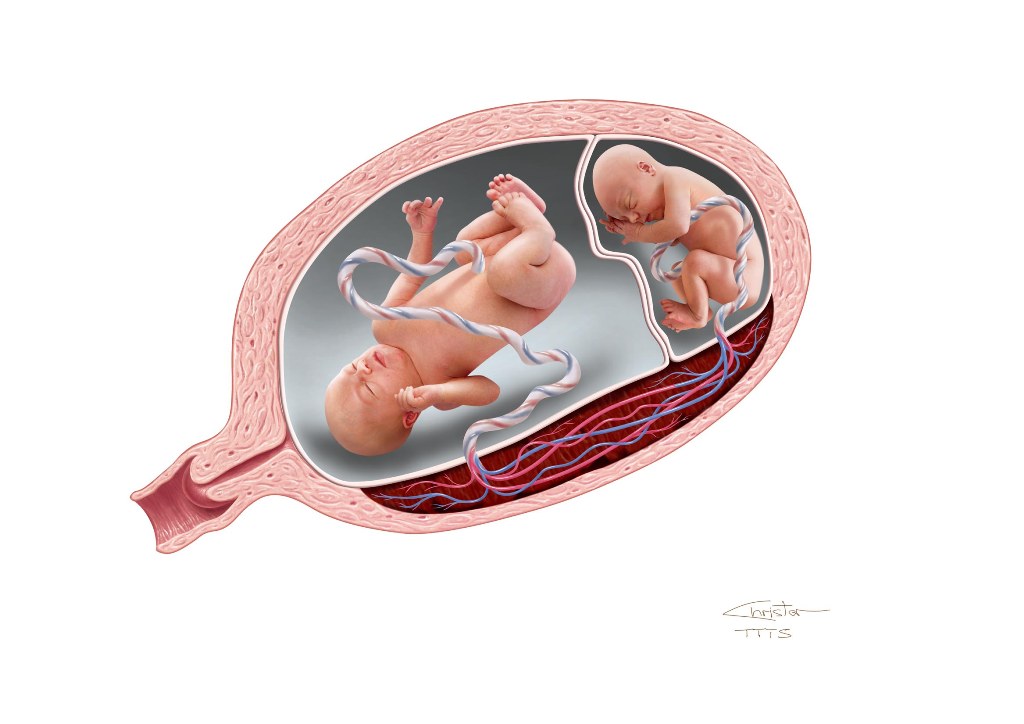

Околоплодный пузырь и плацента: структура и функции